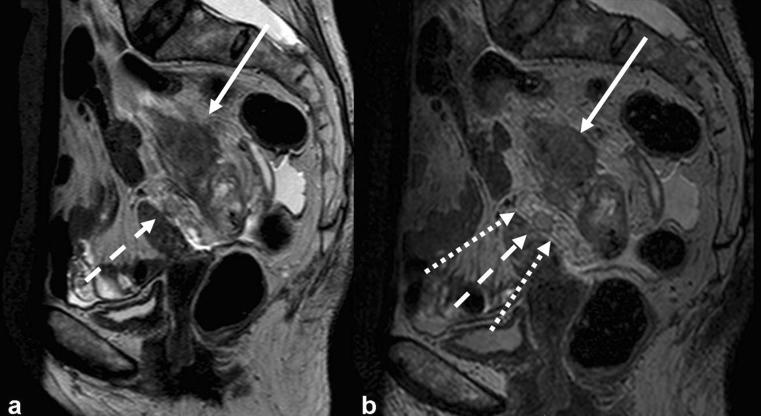

直肠癌的磁共振成像(MRI):全面综述

Magnetic resonance imaging (MRI) in rectal cancer: a comprehensive review.

Magnetic resonance imaging (MRI) has established itself as the primary method for local staging in patients with rectal cancer. This is due to several factors, most importantly because of the ability to assess the status of circumferential resection margin. There are several newer developments being introduced continuously, such as diffusion-weighted imaging and imaging with 3 T. Assessment of loco-regional lymph nodes has also been investigated extensively using different approaches, but more work needs to be done. Finally, evaluation of tumours during or after preoperative treatment is becoming an everyday reality. All these new aspects prompt a review of the most recent advances and opinions. In this review, a comprehensive overview of the current status of MRI in the loco-regional assessment and management of rectal cancer is presented. The findings on MRI and their accuracy are reviewed based on the most up-to-date evidence. Optimisation of MRI acquisition and relevant regional anatomy are also presented, based on published literature and our own experience.

磁共振成像(MRI)已成为直肠癌患者局部分期的主要方法。这归因于几个因素,最重要的是其能够评估环周切缘的状态。不断有一些新进展被引入,如扩散加权成像和3T成像。使用不同方法对局部区域淋巴结的评估也已得到广泛研究,但仍需开展更多工作。最后,术前治疗期间或之后对肿瘤的评估正成为日常现实。所有这些新情况促使我们对最新进展和观点进行综述。在本综述中,对MRI在直肠癌局部区域评估和管理中的当前状况进行了全面概述。基于最新证据对MRI的发现及其准确性进行了综述。还根据已发表的文献和我们自己的经验介绍了MRI采集的优化及相关区域解剖结构。